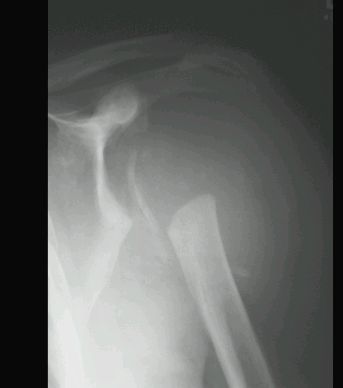

STAW CHARCOTA

RTG